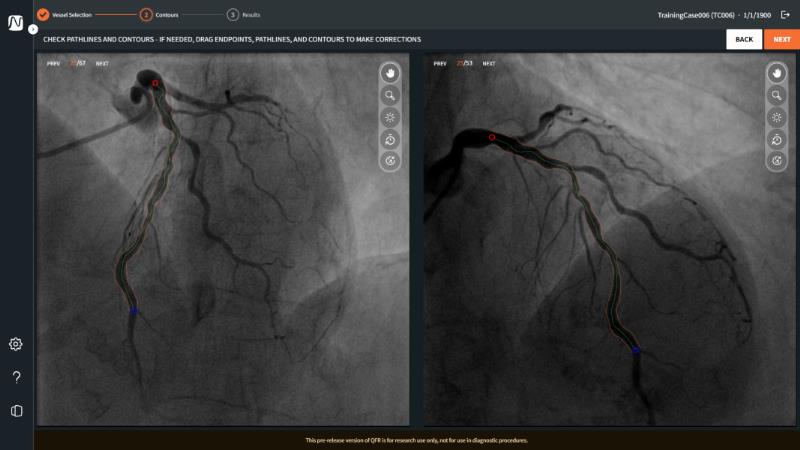

QFR: the next-generation diagnostic tool for epicardial and microvascular disease in the cathlab

Join this session to delve into the cutting-edge capabilities of the newest QFR technology, allowing for rapid coronary vessel analysis in under 30 seconds. Gain insight into the diagnostic potential of QFR-IMR for assessing coronary microvascular dysfunction and understand its implications for patient care. Explore the transformative impact of QFR on treatment planning, paving the way for innovative approaches to managing coronary artery disease.

- To learn how the newest QFR technology enables coronary vessel analysis in under 30 seconds